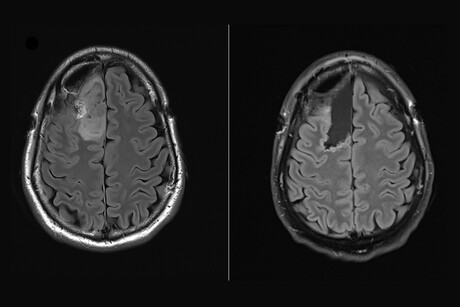

The new trial saw researchers from The Royal Melbourne Hospital, the Walter and Eliza Hall Institute (WEHI) and the Peter MacCallum Cancer Centre (Peter Mac) utilise a drug called Safusidenib — an oral inhibitor targeting the mutated IDH1 gene — observing its effect on LGG tumour samples both before and after treatment. Trial participants took the drug prior to any other cancer treatment — said to be a world first for IDH inhibitors — enabling researchers to assess the activity of this novel treatment within the brain.

“For the first time, we’ve seen what a drug is doing in the brain with incredible detail, helping us to clearly identify the next steps for personalising treatment and predicting who would most benefit.”